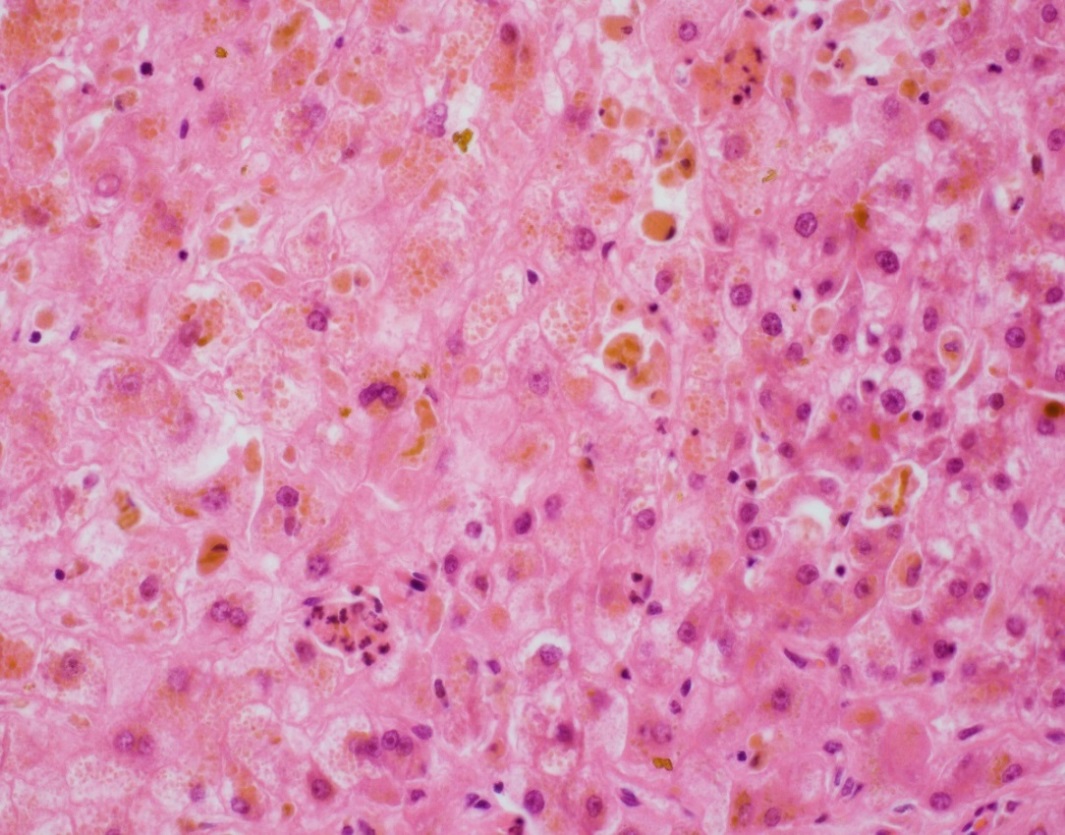

The explant showed submassive hepatocellular necrosis with marked cholestasis, and markedly dystrophic changes in bile duct epithelium in the portal tracts, but there was no ductopenia. Ductular reaction was conspicuously absent. The portal tracts showed mild chronic inflammatory infiltrate, associated with mild focal endothelialitis, and reduced number of small arterial branches. Medium-sized bile ducts showed periductal fibrosis along with dystrophic epithelial changes. Large bile ducts showed foci of intraepithelial lymphocytes, and focal reactive changes. There was central perivenulitis, with foci of lobular microabscesses. There was no foam cell arterial lesion, fibro-muscular intimal thickening, or inflammatory infiltration of muscular arteries. Trichrome stain highlighted fine perisinusoidal fibrosis, extending to portal tracts, but there is no bridging fibrosis. Reticulin showed a largely preserved architecture. A cytomegalovirus immunostain was negative.

Histologic features of chronic rejection and ischemia.

The histologic diagnostic features for CR include presence of dystrophic bile duct epithelium, bile duct loss, and foam cell obliterative arteriopathy. Some cases of late CR have also been reported to show chronic hepatitis-like changes. As has been described with acute presentations of chronic rejection, this case showed prominent inflammatory infiltrate, including endothelialitis and perivenulitis, which initially raised the histologic concern for acute rejection. The patient however remained unresponsive in spite of marked immunosuppressive therapy, and over time in the course of a few months, the inflammation reduced (reflected by the decrease in liver enzymes) whereas the bile duct dystrophy became more conspicuous, characteristically with no ductular reaction. With these clinical and histologic features, this was deemed as an unusual course of CR.